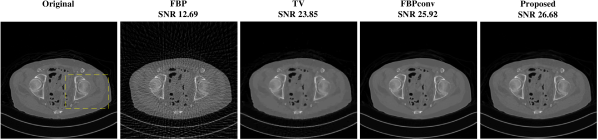

Fig. 2 (a) illustrates the reconstructions of a test image for case when measurement is noiseless. FBP is dominated by line artifacts, while TV satisfactorily removes these but blurs the fine structures. FBPConv and RPGD, on the other hand, are able to reconstruct these details. The zoomed version shows that RPGD is able to reconstruct the fine details better than the others. This observation remains the same when the measurement quality degrades. Fig. 2 (b) shows the reconstructions for 45-dB and 40-dB noise levels. In these scenarios, RPGD40 is significantly better than both FBPconv40 and TV.